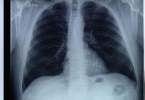

肺是人体重要的呼吸器官和造血器官,人肺有分叶,共有五叶,分为左肺和右肺,右肺比左肺大,左右肺主要是主气和呼吸,其中左肺有两叶,右肺有三叶。当人患有周围性别肺癌或限于肺叶内的不可逆性病变时,经常需要临床上常见的肺叶切除术。

一般情况下需要做肺叶切除的情况较多,需要根据具体情况进行分析。如果肺叶出现肿瘤,需要进行肺叶切除手术,完全清除患病组织,防止肿瘤进一步恶化。此外,当肺叶内出现不可逆性病变或患者患有周围性肺癌时,也需要进行肺叶切除手术。